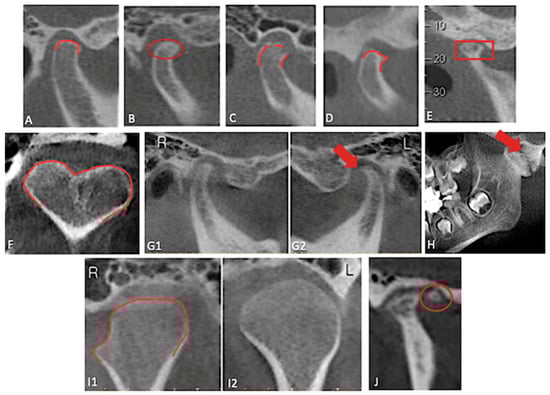

Background/Objectives: The relationship between occlusion and temporomandibular joint is controversial in the scientific literature. The aim of this study is to evaluate the bone changes in the temporomandibular joint and surrounding bone structures and to determine the effect of malocclusions on the temporomandibular joint by making morphometric measurements in different skeletal classes using three-dimensional cone beam computed tomography images. Methods: A total of 90 patients (30 class I, 30 class II and 30 class III) were included in the study. In each skeletal pattern, condylar osseous changes were evaluated and articular eminence inclination and height, condylar diameters were measured. It was also divided into two age groups: 18–29 and 30 and over. Results: Articular eminence inclination measured with the best-fit line method was significantly higher in Class II compared with class I and III, and in individuals aged ≥30 years. Among osseous changes, only condylar flattening showed a significant age-related increase. The mediolateral condylar diameter was greater in males than females, while the anteroposterior diameter was higher in the ≥30-year age group. Conclusions: Temporomandibular joint morphology demonstrates age- and function-related adaptive remodeling, particularly in articular eminence inclination and condylar dimensions. CBCT-based assessment of these morphological features may assist clinicians in diagnosis and treatment planning, although further studies with larger prospective cohorts are warranted.